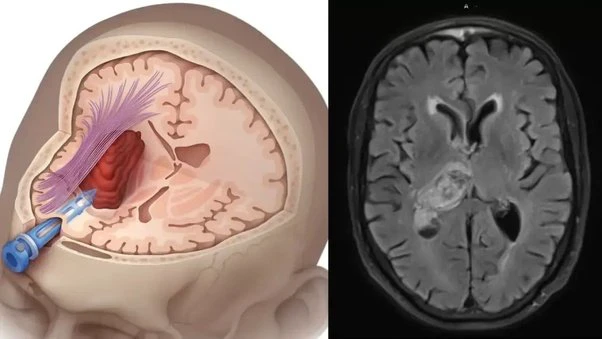

Mini Brain Stroke : ब्रेन स्ट्रोक एक ऐसी जानलेवा स्थिति है, जो बिना चेतावनी के इंसान की ज़िंदगी पलट सकती है। जब मस्तिष्क की किसी नस में ब्लॉकेज हो जाता है और दिमाग तक ऑक्सीजन पहुंचना बंद हो जाता है, तब ब्रेन स्ट्रोक होता है। समय पर इलाज न मिले तो यह मौत का कारण भी बन सकता है।

लेकिन बहुत कम लोग जानते हैं कि बड़े ब्रेन स्ट्रोक से करीब 1 दिन पहले शरीर खुद संकेत देने लगता है। इसे ही मिनी ब्रेन स्ट्रोक या ट्रांसिएंट इस्केमिक अटैक (TIA) कहा जाता है।

मिनी ब्रेन स्ट्रोक भी दिमाग की नस ब्लॉक होने की वजह से ही होता है। NHS के अनुसार, इस दौरान दिमाग को कुछ समय के लिए ऑक्सीजन मिलना रुक जाता है। हालांकि यह स्थिति स्थायी नहीं होती और अक्सर 24 घंटे के भीतर अपने-आप ठीक हो जाती है।